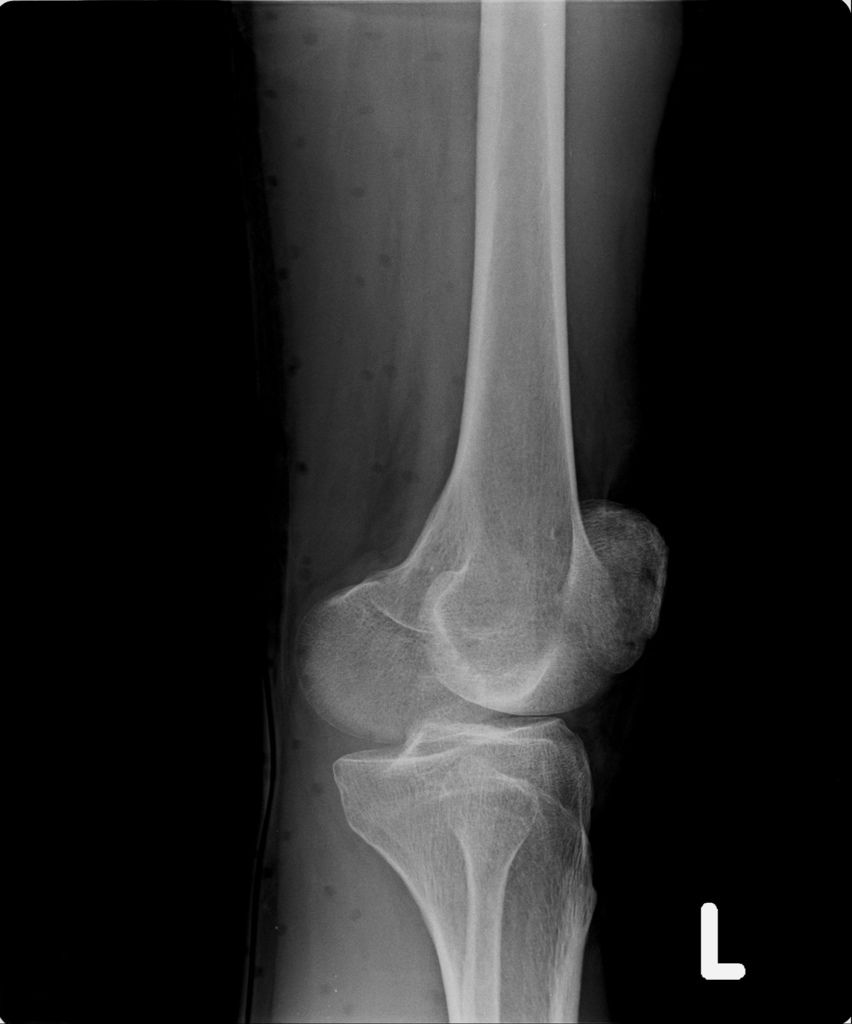

左腳X光↓

左腳X光照↓

進入門診前,我自認為手比腳恢復還快,因為比起一開始,手指比較能出力了,手腕可轉動的範圍也變大了。腳因一直用副木石膏固定住,不能動,所以也不知恢復多少。進入門診後,黃醫師說斷裂的骨頭都沒移位。手沒什麼進展(骨頭不會長那麼快),腳的部份下回再來復診時,可能會恢復的較快了。